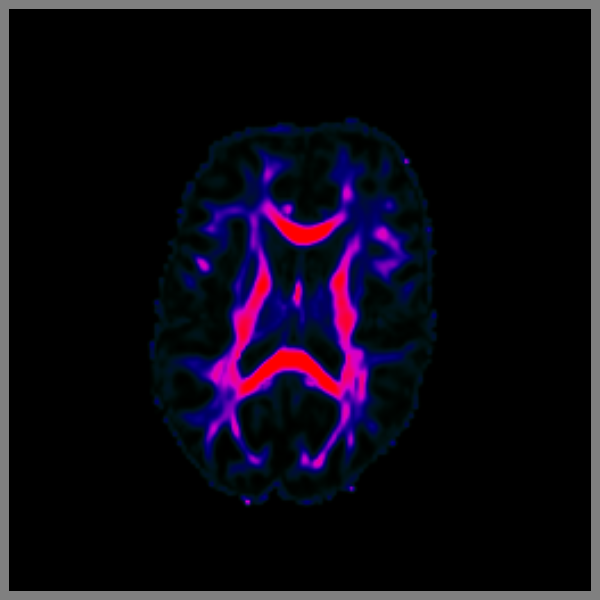

Render slices from FA with your colormap#

It is also possible to set the colormap of your preference. Here we are loading an FA image and showing it in a non-standard way using an HSV colormap.

lut = actor.colormap_lookup_table(

scale_range=(fa.min(), fa.max() * 0.8),

hue_range=(0.4, 1.0),

saturation_range=(1, 1.0),

value_range=(0.0, 1.0),

)

This is because the lookup table is applied in the slice after interpolating to (0, 255).

fa_actor = actor.slicer(fa, affine=affine, lookup_colormap=lut)

window.record(

scene=scene, out_path="slices_lut.png", size=(600, 600), reset_camera=False

Simple slice viewer with an HSV colormap.